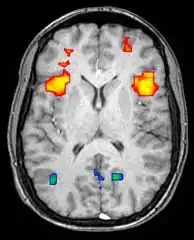

![]() Para-sagittal MRI of the head in a patient with benign familial macrocephaly | |